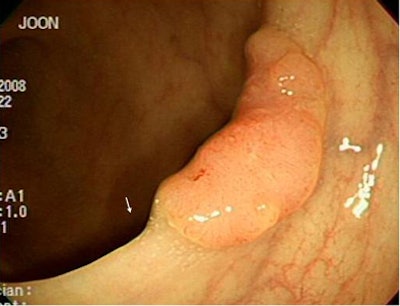

![]() |

| Electronic cleansing artifacts caused false positives resulting from untagged feces, pseudoenhancement of tagged materials (above), and air-contrast-wall interface (below). |